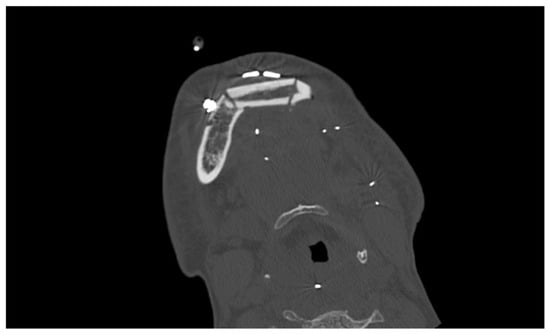

2. Case Report